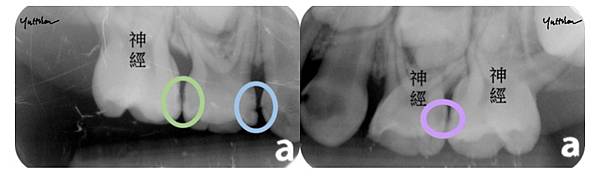

圖中可以看到口內看起來沒有蛀牙的地方

其實在X光下已經有明顯的蛀牙